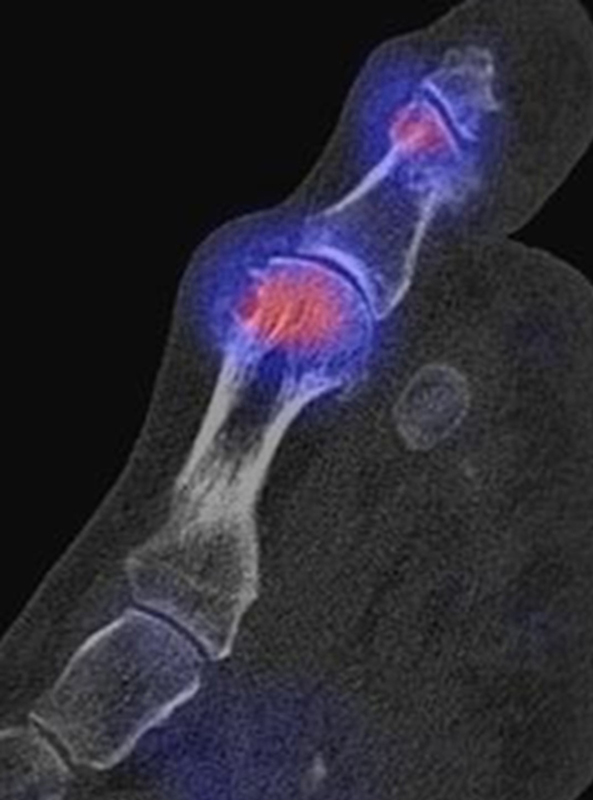

Abbildung 1.6.

Bekannte Gicht mit Polyarthralgien. Am rechten Großzehengrundgelenk lateral in der Grundphalanx entzündliche Erosionen.

Zum Lesen der Bildbeschreibung und zur Vollansicht bitte das Bild anklicken. Bild: H. C. Rischke

Abbildung 1.7.

Gichtarthritis mit Osteolysen und flauen Verkalkungen in den periartikulären Weichteilen/Gelenkkapsel.